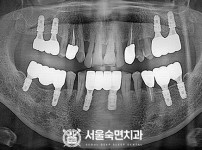

임플란트-전후사진1

치과를-선택할-때-꼭-확인하세요-서울숙면치과-임플란트-전후사진